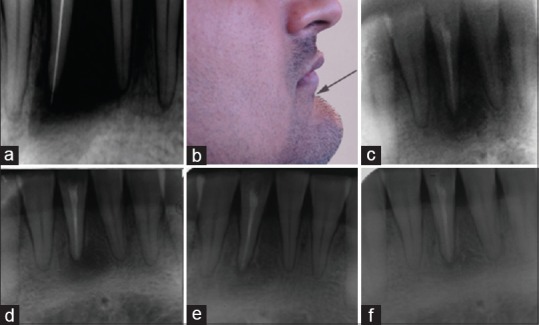

根管囊肿(RC)是影响颌骨的最常见的牙源性炎性囊肿,累及龋齿或外伤性非重要牙齿的根部。针对此类病变的治疗,人们提出了不同的治疗方法,如非手术牙髓治疗或带有原封闭、减压等功能的外科根管治疗。本病例是一名 28 岁的健康男性患者,他报告说 41 号牙、31 号牙和 31 号牙出现疼痛和肿胀。根据临床、放射学和细针穿刺细胞学检查,确诊为罕见部位的感染性 RC。考虑到临床特征、起源、延伸、囊性病变的大小和患者的合作情况,采用了巴斯克假说的非手术牙髓疗法。术后一年的结果表明,非手术牙髓治疗和利用巴斯克假说的微创治疗是将感染性根尖囊肿病变转化为健康根尖周牙周组织的有效工具。

Radicular cyst (RC) is the most common odontogenic cyst of inflammatory origin affecting the jaws; involves the roots of the carious or traumatic non-vital tooth. Different therapeutic modalities, such as nonsurgical endodontic therapy or surgical enucleation with primary closure, decompression etc., were proposed for the management of such lesions. Presenting a case of a 28-year-old otherwise healthy male patient who reported with pain and swelling with respect to tooth #41, 31. Diagnosis of infected RC at a rare location was established on the basis of clinical, radiographical and fine needle aspiration cytological examination. Looking after the clinical characteristics, origin, extension, size of cystic lesion and patient cooperation; nonsurgical endodontic therapy utilizing Bhasker's hypothesis was opted. One year post-operative result suggested that nonsurgical endodontic therapy along with minimally invasive treatment utilizing Bhasker's hypothesis is an effective tool to transform infected radicular cystic lesion to healthy periapical periodontal tissue.